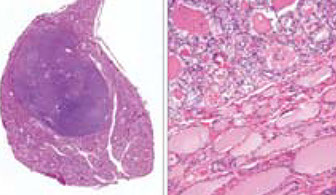

Parathyroid adenoma

Parathyroid adenoma with rim of normal parathyroid tissue and small b9 cyst

Histo: Normal rim of tissue usually present around a parathyroid adenoma

- multiple adenomas are possible but less common than a single adenoma (thus if 1 gland is enlarged on RFS c little fat [<50%, questionable]and rim of normal tissue, may suggest parathyroid adenoma, BUT...)

- since differentiating bwt adenoma and hyperplasia NOT possible on RFS, best to dx "enlarged parathyroid gland" (done by weight)